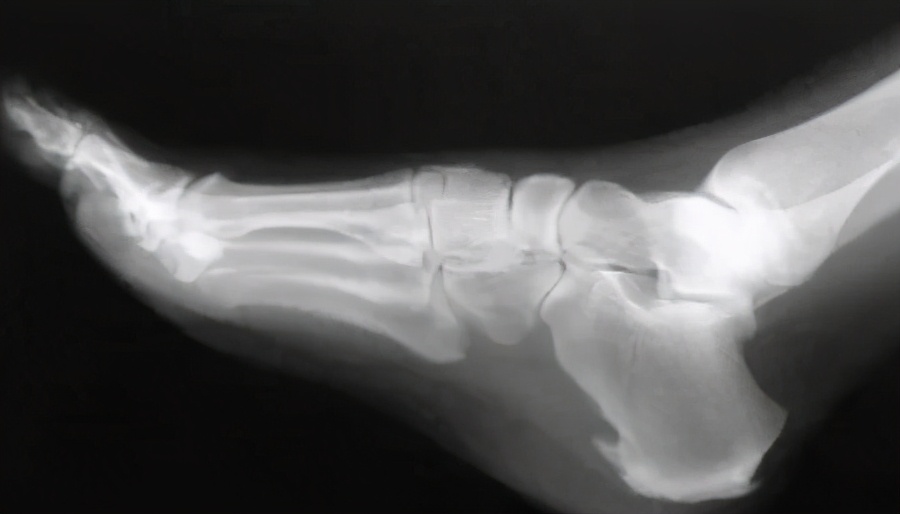

跟骨骨刺

这里专门说下临床常见的跟骨骨刺,病员一般描述是走路的时候脚底非常疼,一看X线片上跟骨底部那长长的骨刺就不寒而栗地说:“医生,就是这个骨钩把我弄得这么疼的,你帮我把它手术割掉吧?”其实跟骨骨刺临床常见,手术把它割掉一定不是一个好办法,因为力学结构的变化,其实割掉以后不注意的话还是会再长出来的,何医生要告诉你的处理方式是:鞋垫厚点、软点,鞋子可以大一号,注意改变一下脚部的受力点,用物理方式对足底部的症状进行缓解就可以了。手术是确实不建议的哈。